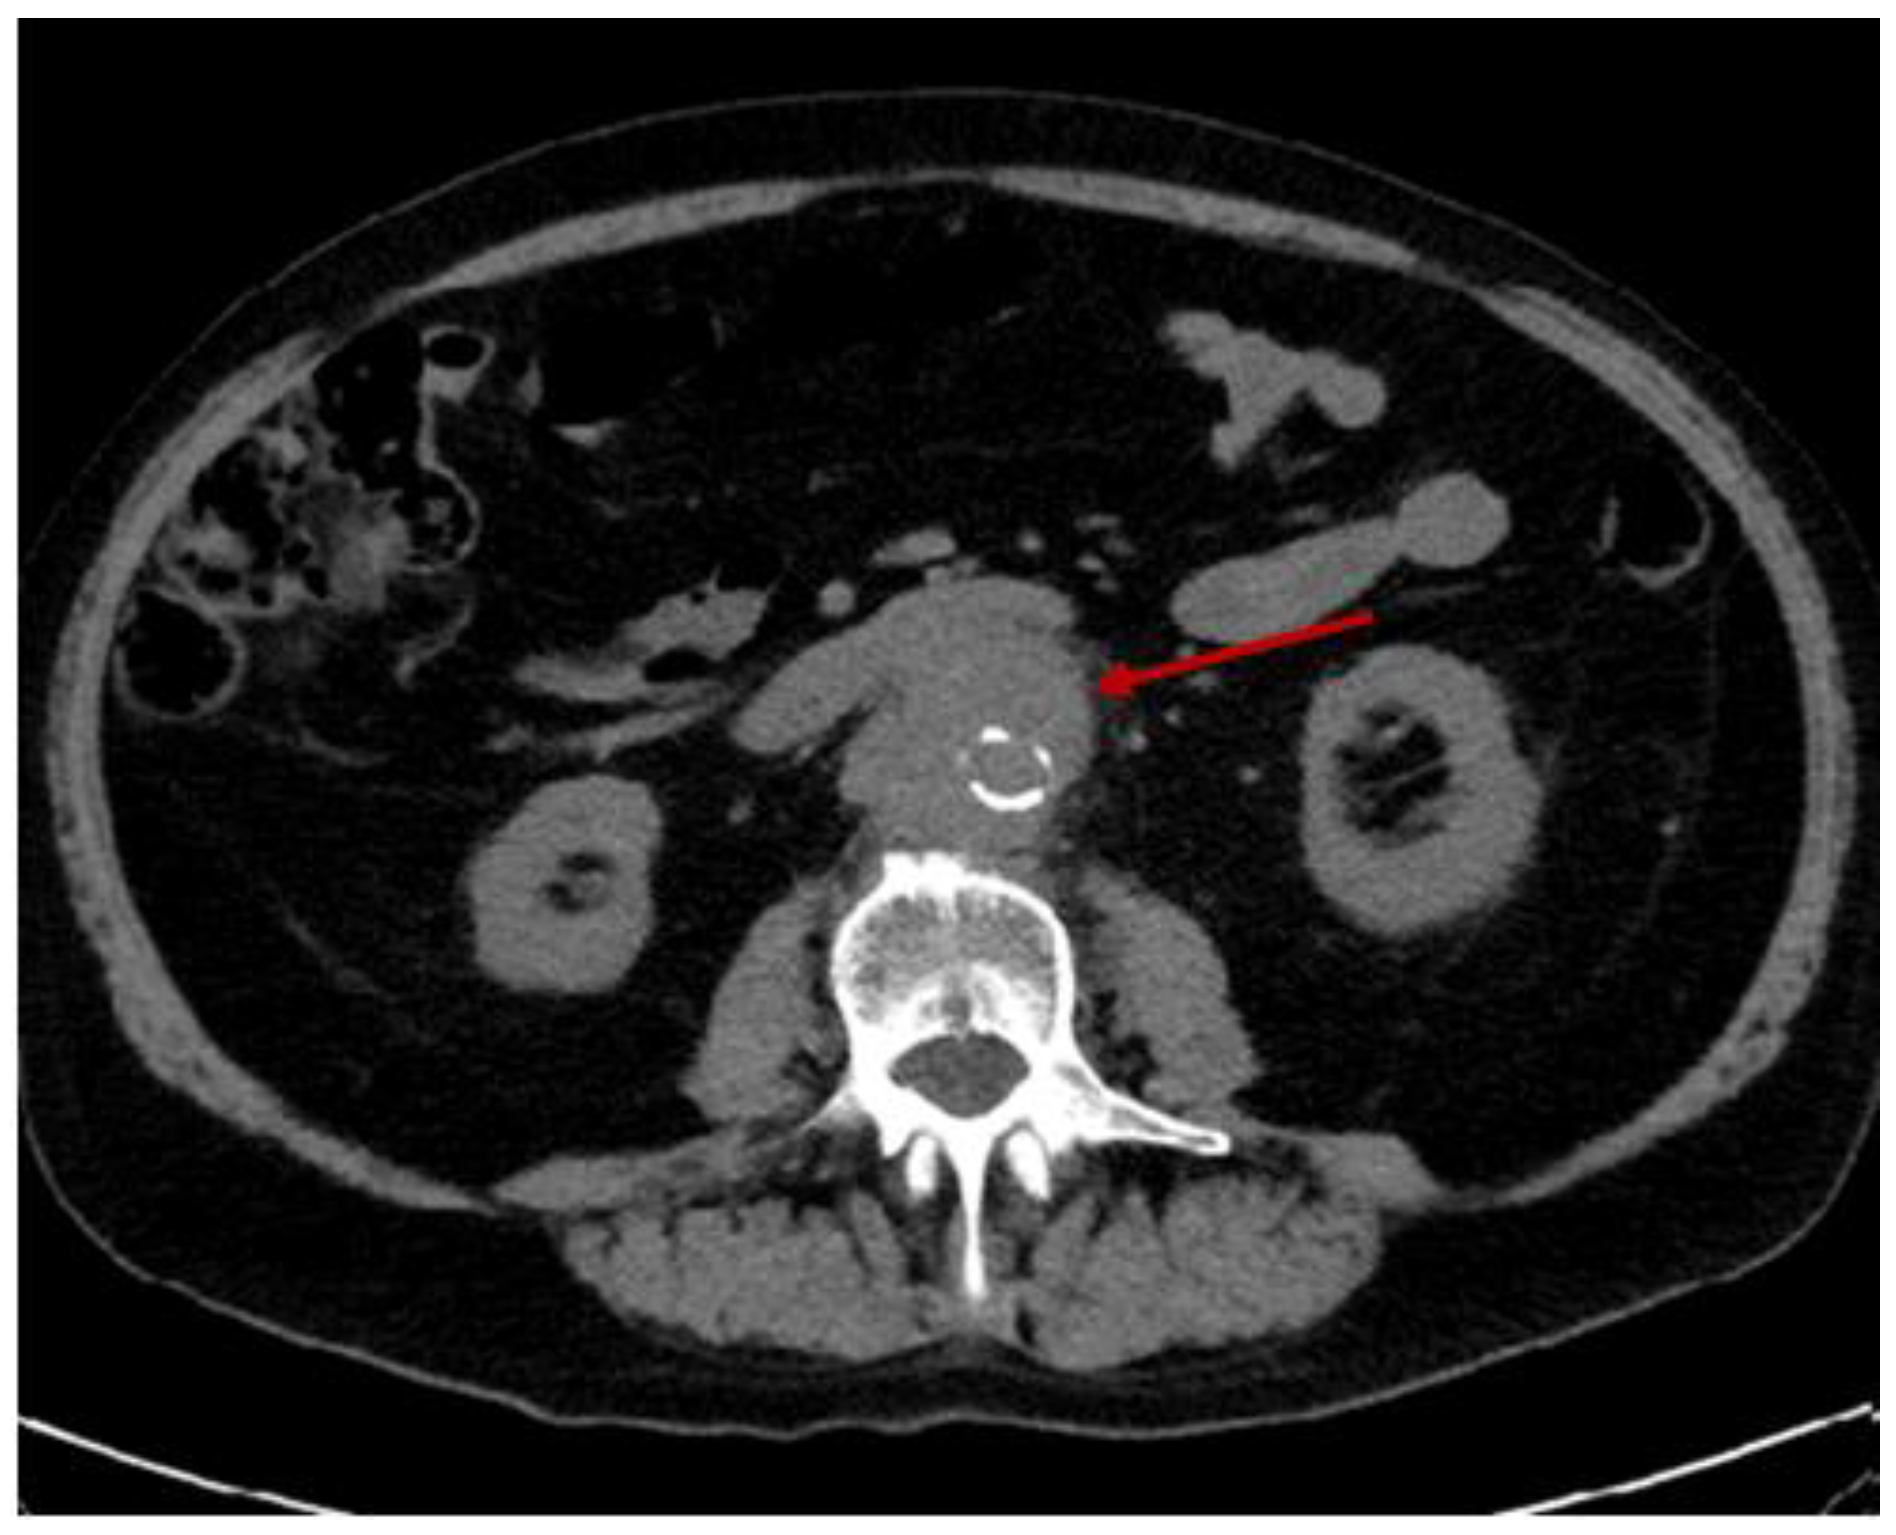

3.2.2. Additional Imaging Assessments

3.2.3. The Descending Aorta Rupture